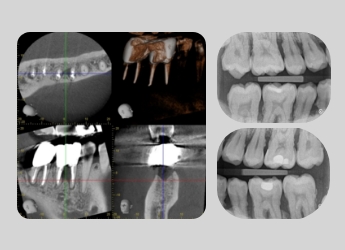

咬翼法

咬翼法(バイトウィング)は、むし歯や歯周病の状態を正確に把握するためのレントゲン検査です。歯と歯の間の見えにくいむし歯や、詰め物・被せ物の適合(二次カリエス)、歯石の沈着などの確認に有効です。